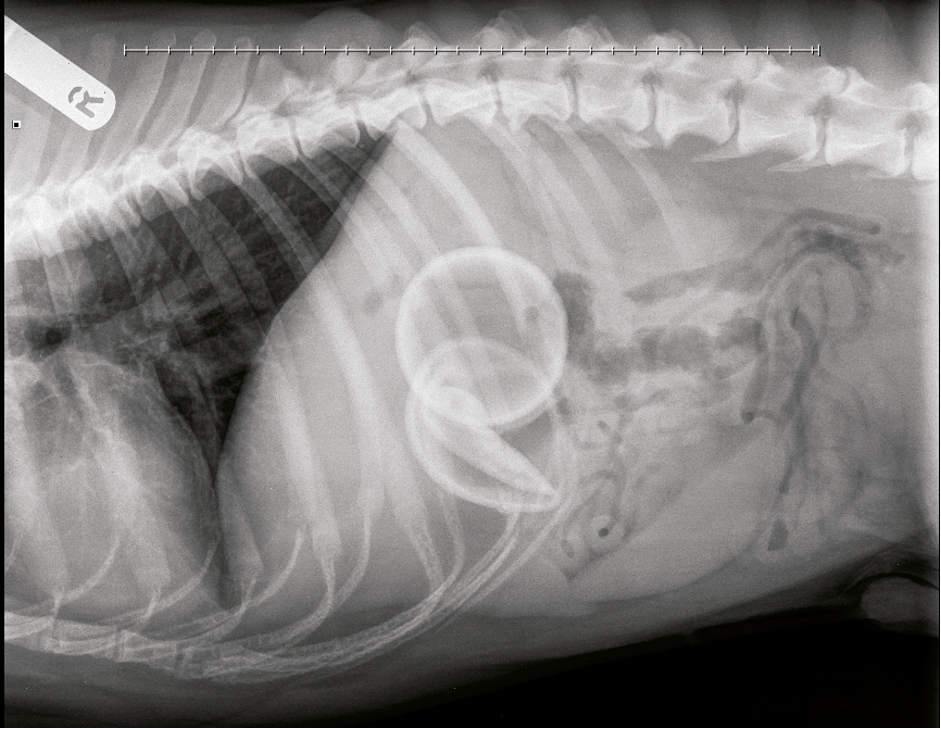

Dog recovers after swallowing two tennis balls!

Cross-breed Loki is recovering after emergency surgery to remove two tennis balls from his stomach. The five-year-old dog was rushed to Wolverhampton PDSA Pet Hospital when he refused to eat and started being sick.

After X-rays revealed the cause of the blockage, vets were able to remove both balls intact. PDSA vet Catherine Burke said that tennis balls can get stuck at the back of a dog’s throat, causing them to choke, or blocking their airway. She added that the abrasive felt layer of these balls can have a sandpaper-like effect, wearing down canine teeth over time and causing pain and difficulty chewing.